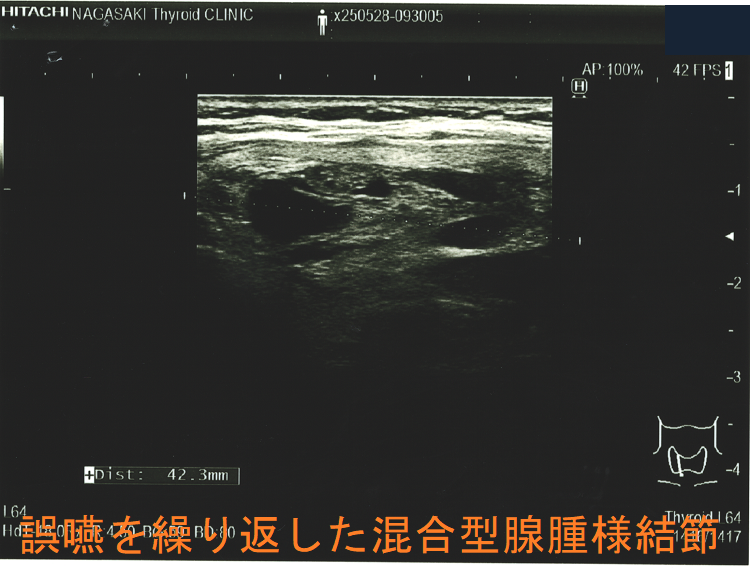

胸骨下まで伸びた巨大甲状腺腫による食道圧迫は、嚥下障害と食道咽頭逆流を生じ、誤嚥性肺炎の原因になります(Korean J Intern Med. 2016 Nov;31(6):1196-1197.)

誤嚥を繰り返した混合型腺腫様結節